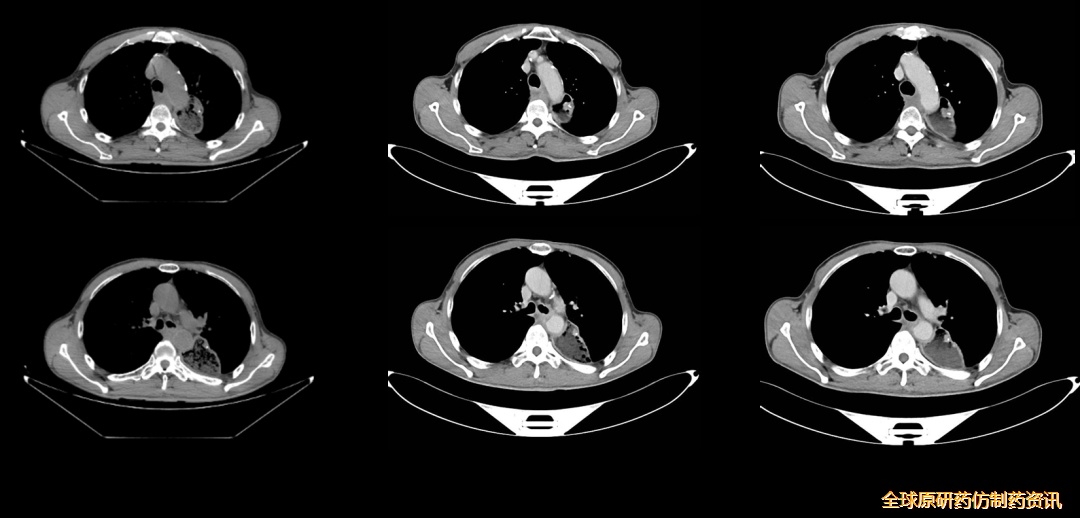

图1 影像学检查(2024-07-10)

2024-07-10,PET-CT示:左侧胸腔胃,吻合口区FDG代谢未见增高;后纵膈不规则形软组织影,FDG代谢异常增高,SUVmax=7.6,与气管、降主动脉、胸椎前缘界限模糊,前方气管受压、向气管内突入,考虑食管癌术后转移,累及气管、降主动脉、胸椎前缘。